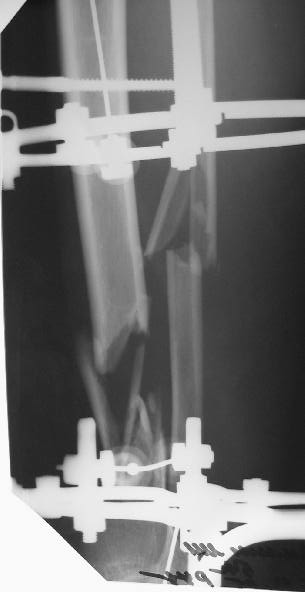

Больному 7 дней назад плита придавила голень стопу. Диагноз Открытый ( 3 б по Каплану) сложный многооскольчатый перелом с выраженным раздроблением н/3 диафиза голени, перелом лодыжек без смещения, перелом основания 5 плюсневой кости с небольшим смещением.

По моему мнению во-первых нужно гешить проблему мягких тканей, для этого провести вторичную и третичную и сколько понадобится обработок при этом удаляя все свободные и инфицированные костные фрагменты - безжалостно и после этого надежное закрытие кожного дефекта с запасом, лучше всего микрохирургический соседистый лоскут . Когда мягкие теани будут готовы в зависимости от размера дефекта можно решить что делать. Лично я предпочитаю замещение дефекта по Илизарову в классическом варианте - остеотомия проксимального отдела тибии и дистальное перемещением с формированием регенерата. Тем более аппарат уже есть. Я бы не стал фиксировать стопу. Судя по снимку дистальный фрагмент достаточно большой, но посмотрим что останется после последней ХО.

Согласен с коллегами , что фиксация стопы тут избыточна, и что дефекта не видно.

На дополнительных снимках итраоперационно видна значительная потеря массы (рис 6 рис 1). Хотя на снимках контрольных после операции вроде дефекта значительного нет. Все же придется, как-то замещать дефект костный на голени, думаю подготовить морально больного к повторной операции костной пластике, после заживления ран.

1. Дождаться заживления ран и через 2-3 месяца после заживления провести свободную костную аутотрансплантацию.

2. Провести остеотомию сегментарную м/берцовой кости напротив дефекта и медленно этот сегмент подвести с помощью спиц в место дефекта. Можно не дожидаться полного заживления ран.

Можно сделать несвободную пластику - через прокол сформировать отщеп длиной 3-4 см долотом на медиальной поверхности кости (чтобы мышцы не вовлекать), и спицей-крючком утянуть его в дефект. Ждать тут особо нечего, можно начинать хоть вчера.